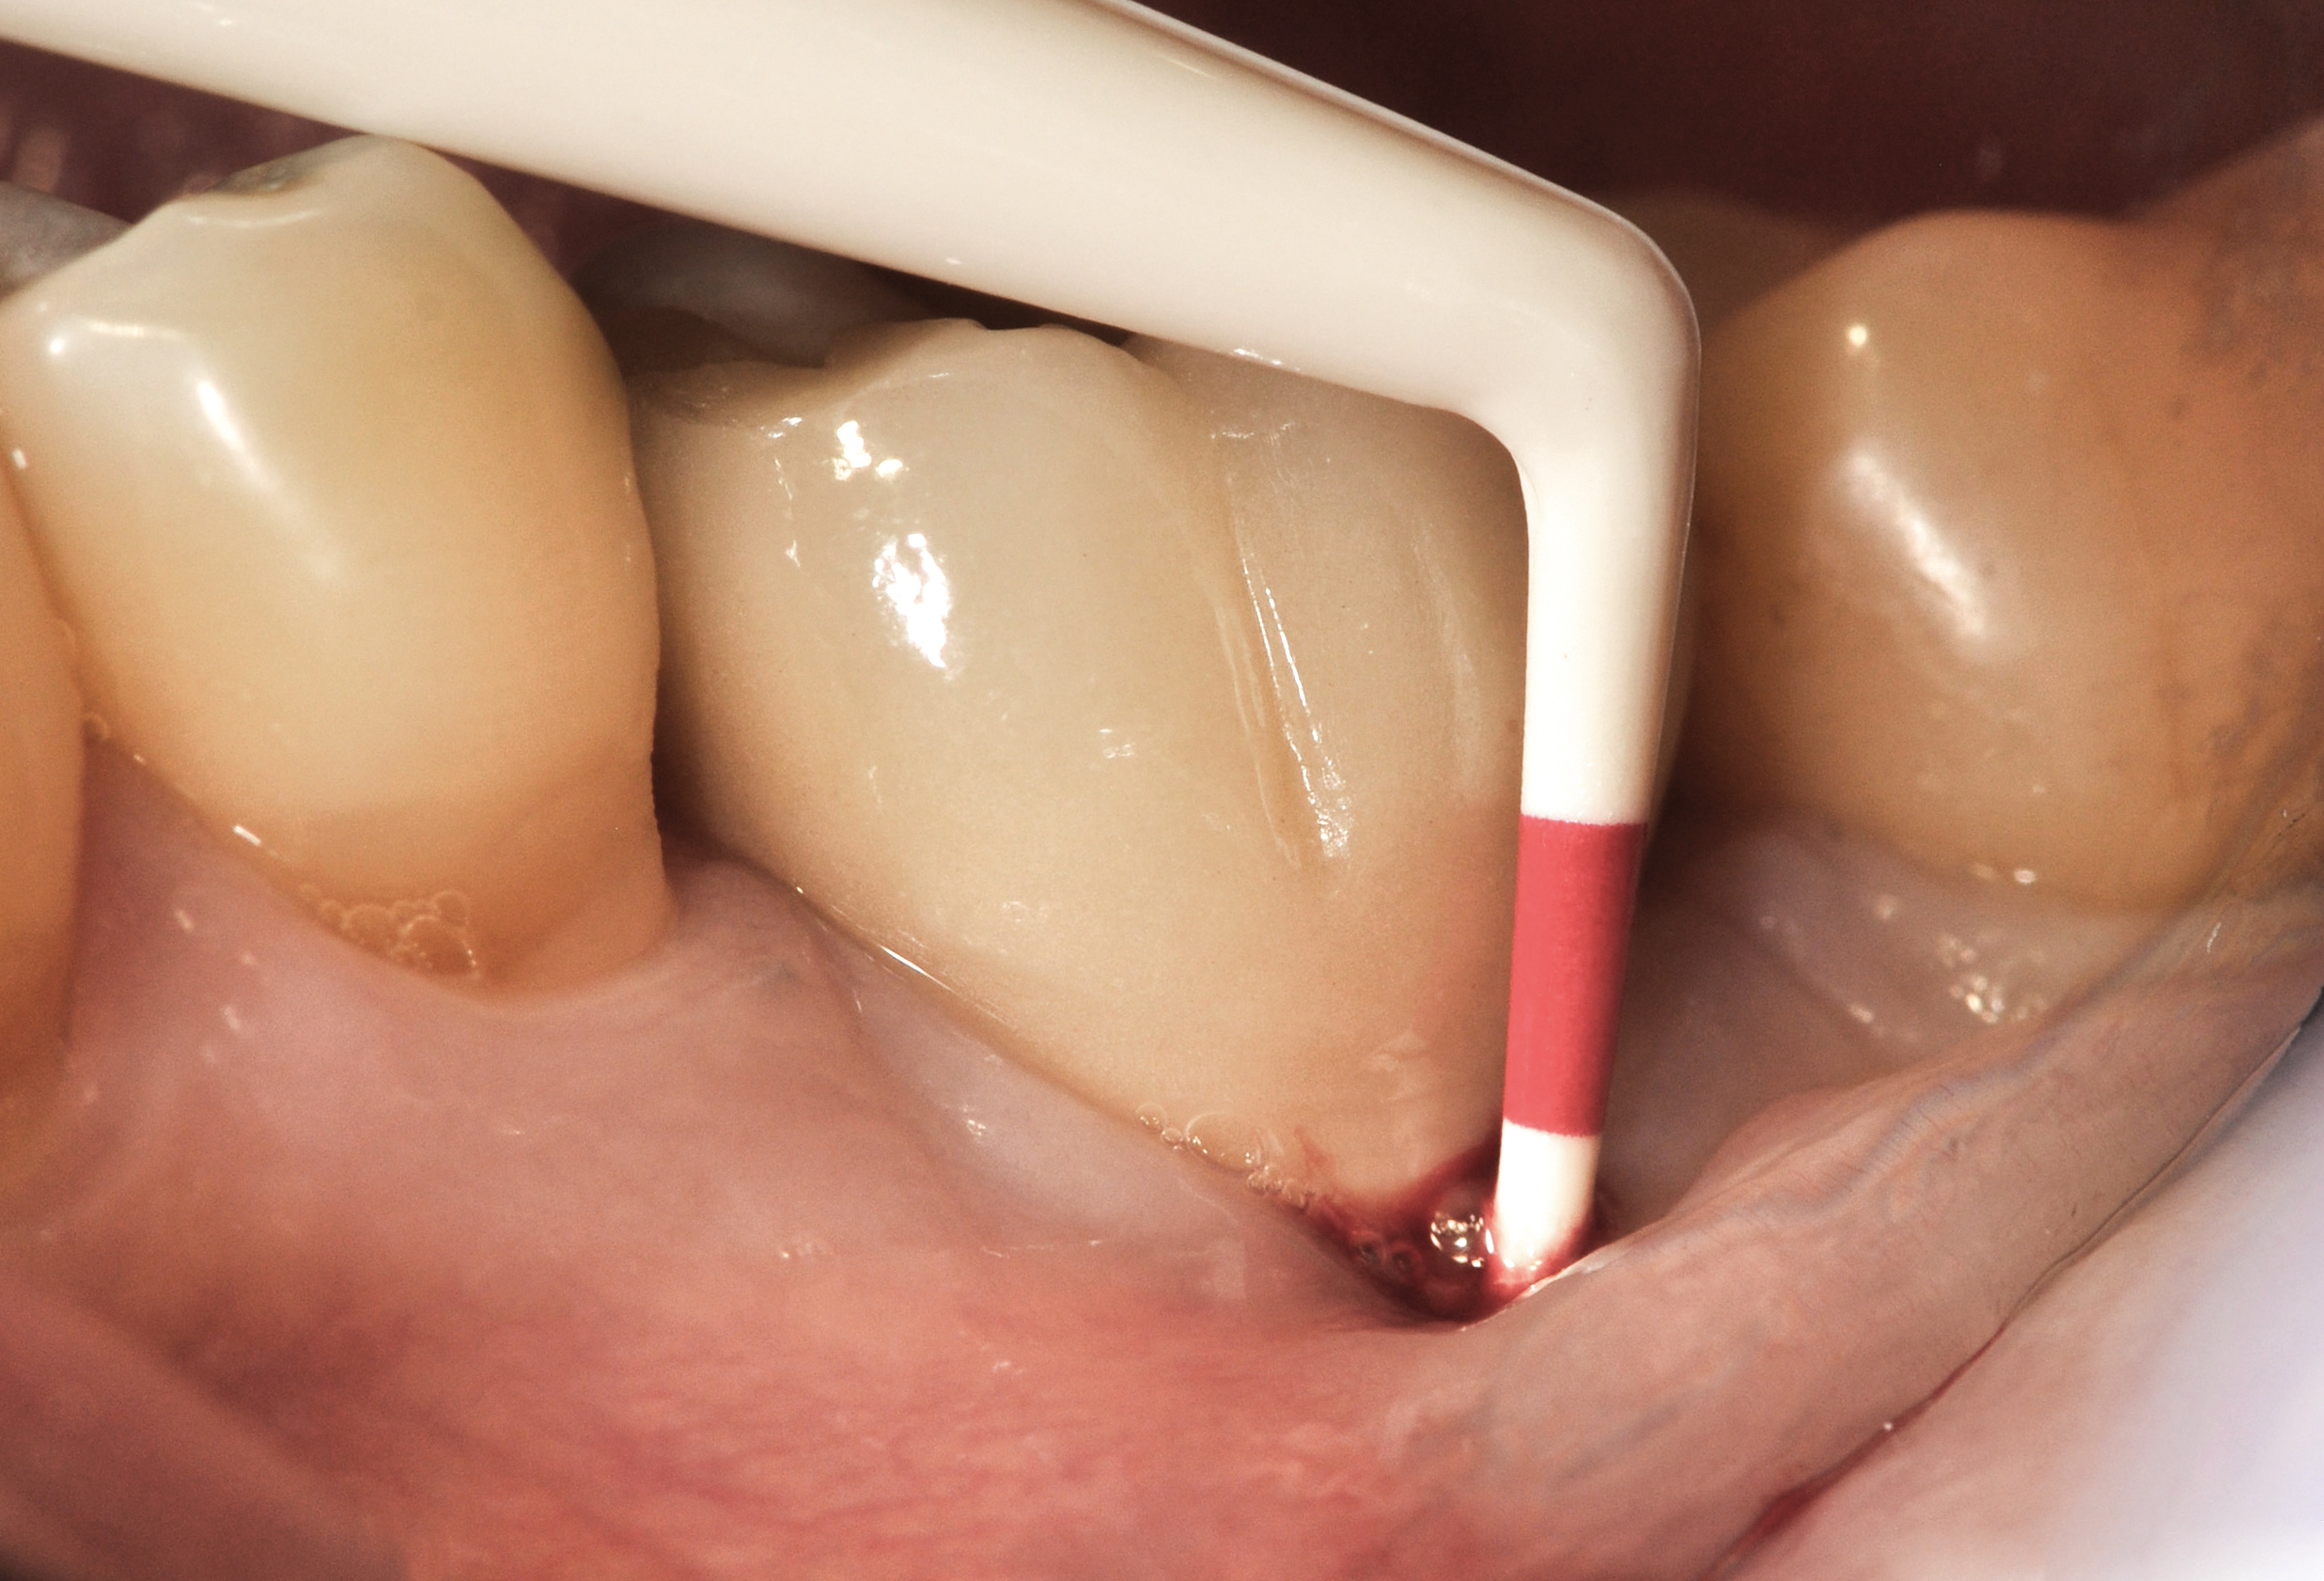

Clinical examination showed 2 mm of buccal recession with a shallow vestibule and absence of keratinized attached gingiva against the crown with 8 mm of circumferential pocketing accompanied by bleeding upon probing (Figure 15 and Figure 16). A periapical radiograph showed a symmetrical vertical osseous defect causing the loss of 50% of the bone around the implant (Figure 17). Because the patient had made a significant investment of time and finances to replace her lost tooth with the implant, she desired that the implant and restoration be retained, if feasible.

Fig 15. The implant-supported restoration of tooth No. 19 presented with a lack of attached keratinized gingiva, shallow buccal vestibule, and 2 mm of buccal recession.

Fig 16. The restoration exhibited an 8-mm pocket upon probing, with bleeding on the buccal aspect.